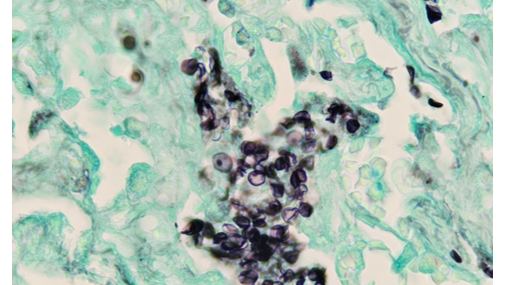

21-летний мужчина, не имеющий в прошлом серьезных заболеваний, поступил в отделение неотложной помощи с острой гипоксемической дыхательной недостаточностью. Он также сообщил о продуктивном кашле с зеленой мокротой и непреднамеренной потере веса на 30 фунтов за последние 5 месяцев. При поступлении насыщение кислородом было на уровне 80, а первоначальные анализы показали молочнокислый ацидоз и реактивный ВИЧ Ag/Ab. Его вирусная нагрузка ВИЧ составляла 1 359 029 копий/мл при количестве CD4 37 клеток/мм3 ...